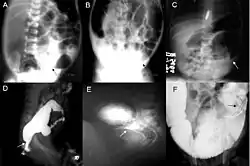

Diagnóstico

O diagnóstico definitivo é feito por biópsia por sucção do segmento estreitado distalmente.[26] Um exame histológico do tecido tem por objetivo mostrar a falta de células nervosas ganglionares. As técnicas de diagnóstico envolvem manometria anorretal,[27] enema baritado e biópsia retal. A biópsia retal por sucção é considerada o padrão ouro internacional atual no diagnóstico da Doença de Hirschsprung.[28]

Exames radiológicos também podem ajudar no diagnóstico.[29] A cineanografia (fluoroscopia do meio de contraste passando pela região anorretal) auxilia na determinação do nível dos intestinos afetados.[30]